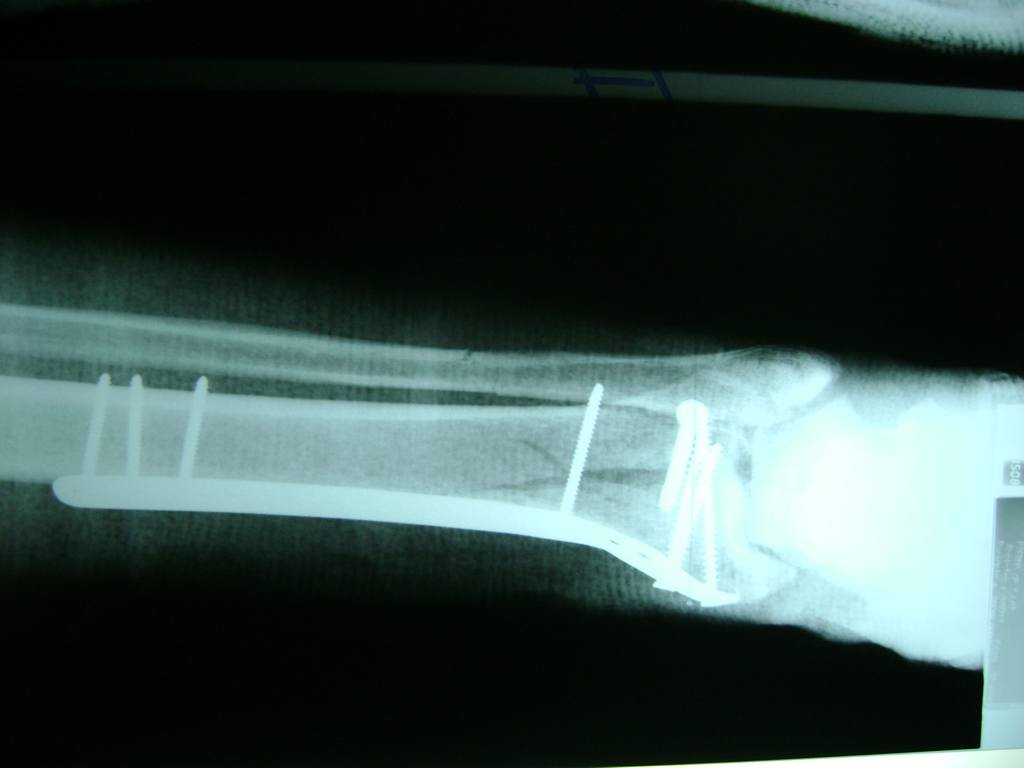

Cuando se necesita cirugía, es probable que esta implique el uso de clavijas de metal, tornillos o placas para sostener los huesos en su lugar mientras la fractura se consolida. Los elementos de soporte pueden ser temporales o permanentes.

Algunas fracturas de tobillo pueden requerir cirugía si:

- Los extremos de los huesos están desalineados entre sí (desplazados).

- La fractura se extiende hasta la articulación del tobillo (fractura intra-articular).